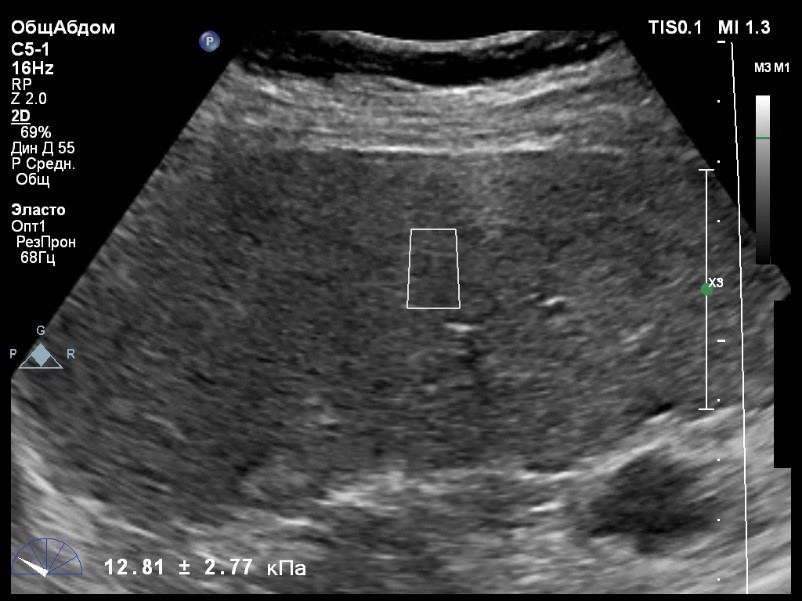

Пациент обратился к доктору с направлением на исследование степени жесткости печени в ноябре 2017 года. Из истории болезни, пациент страдает Гепатитом С с 2002 года. Закончила противовирусное лечение в мае 2017 года. В сентябре 2016 года, с помощью транзиентной эластографии была установлена медиана жесткости печени 45 kPA. На момент настоящего исследования, пациент не принимал пищу на протяжении 4 часов, АСТ, АЛТ не превышают патологических значений. В виду технических сложностей выполнения исследования (узкие межреберные промежутки), для оценки жесткости была выбрана технология компании Philips ElastPQ (точечная эластография) и прибор компании Philips Epiq 7. Исследование было проведено в соответствии с клиническими рекомендациями для ультразвуковых приборов компании Philips. В результате исследования были получены следующие результаты:

| 1 [17.28] kPa | 2 [13.59] kPa | 3 [14.47] kPa |

| 4 [16.71] kPa | 5 [18.48] kPa | 6 [21.20] kPa |

| 7 [21.36] kPa | 8 [15.64] kPa | 9 [19.95] kPa |

| 10 [19.89] kPa | 11 [22.14] kPa | 12 [16.48] kPa |

| 13 [16.41] kPa | 14 [22.02] kPa | |

Стандартное Отклонение [2.75] kPa Медиана Жесткости [17.88] kPa Фактор Качества IQR/Med 9%

Зона интереса расположена на более чем на один сантиметр глубже капсулы, параллельно ходу луча, в середине изображения, в участке печени лишенном артефактов.

Капсула видна как белая линия перпендикулярная ходу ультразвукового луча, исследования производятся приблизительно в одном и том же сегменте печени.

Для интерпретации полученных клинических данных были использованы Рекомендации по проведению эластографии сдвиговой волной для оценки жесткости печени при использовании ультразвуковых аппаратов компании Филипс с примером протокола. Следует отметить достаточно высокую жесткость печени у пациента по данным предыдущих обследований и низкую активность основного заболевания по данным биохимических проб, что является показанием для динамического наблюдения и оценки жесткости печени. Отмечу, что для проведения исследования у данного технически сложного пациента был совершенно обоснованно выбран аппарат экспертного класса. Подготовка пациента соответствовала проводимому исследованию. Представленные слайды проведенного исследования свидетельствуют о правильном техническом исполнении проб, что позволяет заключиться о достоверности полученных измерений. Таким образом, учитывая полученную медиану жесткости на уровне 17,88 кРа (13.59 -22.02 kPa) и уровень стандартных отклонений не превышающих 30%, полагаю, что уровень степени фиброза соответствует стадии F4. Заведующий отделением УЗД МЦ «Асклепий», Глушенко Д. Е.